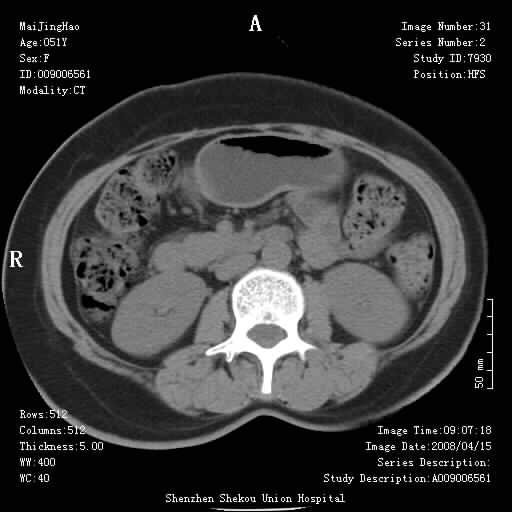

以下是引用余辉在2008-4-26 8:55:00的发言:[br]患者有结石史,此次腹痛4小时,胆总管全程扩张,应有胆总管末端梗阻,此次仍考虑胆结石症,积气不外两种原因,一种是结石下移时肠道内气体逸入,其次为产气菌感染。(倒数第三幅图像于扩张之胆总管末端似可见稍高密度影,考虑为结石影)

以下是引用听蝉观竹在2008-4-26 11:41:00的发言:[br]胆道手术分两种情况:[br]1、如果仅仅做胆囊切除手术,肝内胆管不会积气,只会出现胆总管代偿扩张,因为奥迪氏括约肌依然功能正常胆道与外界并不相通;[br][br]2、胆囊切除+胆总管空肠吻合手术(即roux-y式),则肝内胆管会出现积气,只是因为胆管与小肠相通,气体来源于小肠。这是临床十分常见的手术。[br][br]这个病例应该是胆囊切除+胆总管空肠吻合手术,是正常手术后表现,并不是胆道感染的表现。